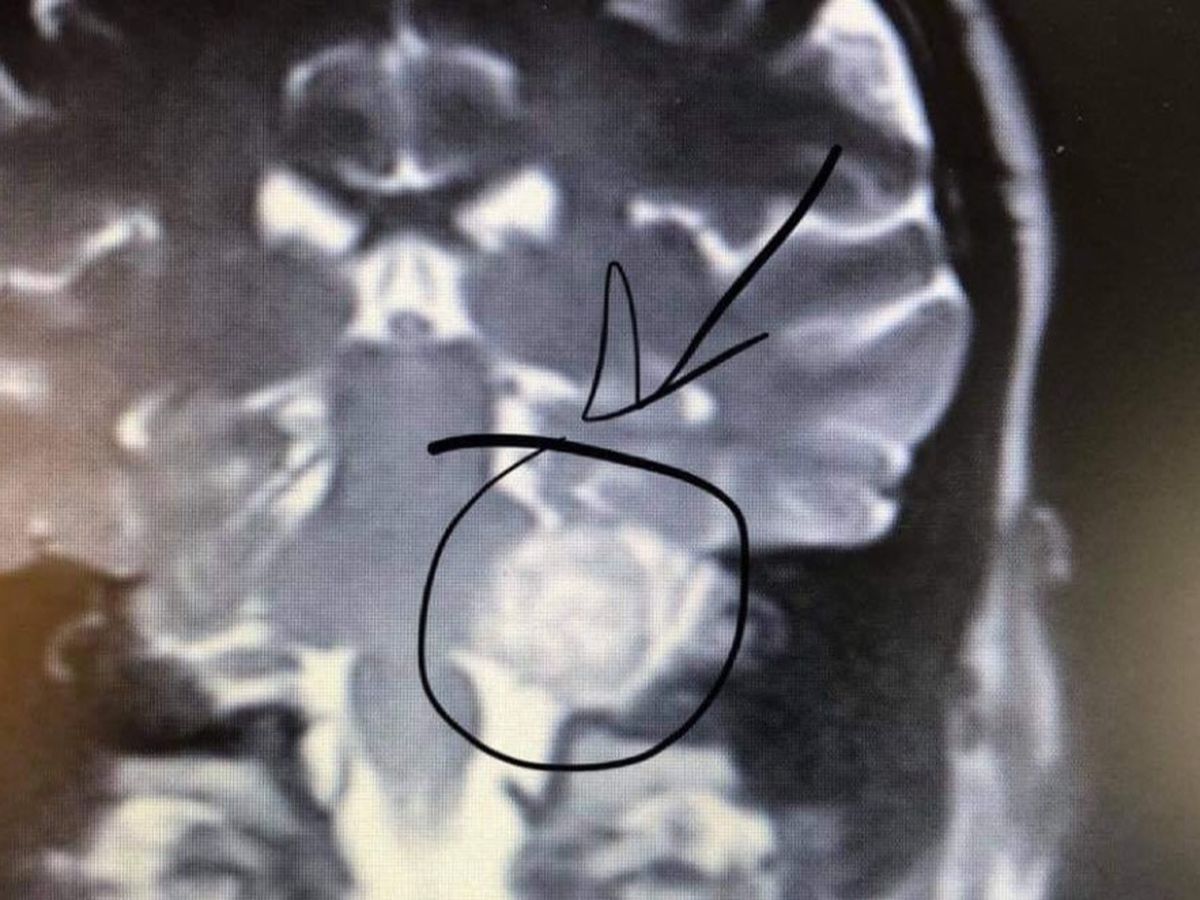

Pete Corrigan is a veteran of the US Air-force and he served our country for more than 6 years. After his brave years of service he used the GI Bill to earn a BS in computer science, where he then worked hard to become the CIO for over 30 clients learning the ins and outs of their business. Unfortunately life never wraps up perfectly in a bow and it's what happened in 2018 that has brought us here today. In 2018 Pete had severe hearing loss in his left ear and the left side of his face was having a numbing sensation. Per the usual back and forth to the doctors he saw a neurologist who ordered an MRI and that is when the tumor was discovered.

Pete has a rare tumor that grows out from his ear canal, and into his head. This type of tumor only occurs in about 2,000 people per year. The tumor is large and it is near his brain stem, in 2018 Pete had surgery to remove a portion of the tumor. In this process Pete lost his hearing, and had to relearn how to walk. The medical professionals tried gamma knife radiation on Pete to try and avoid more surgeries, but were unsuccessful. Pete has worked hard to build Princeton microgreens something he got into after the first surgery, He has provided some of the most valuable content to our community, some of which I have yet to see covered by others. Now as they face decisions as a family, we want them to know that they have the support of the community. None of us ever know what tomorrow brings and while we don't have the power to solve all the worlds problems we can provide a little relief to people throughout our life.